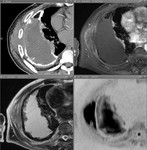

[画像診断]肋骨の線維性骨異形成(fibrous dysplasia)について 2011-05-02